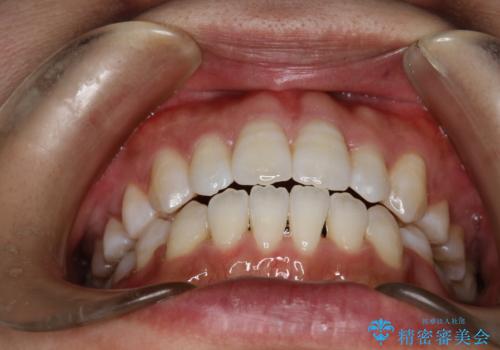

ガタガタがなくなり、上下の前歯が接触すようになり、見た目とともに咬みやすくすることができました。

左側の上下の前から4番目の歯を抜歯して、矯正することとしました。

装置は表側のワイヤーを選択されました。